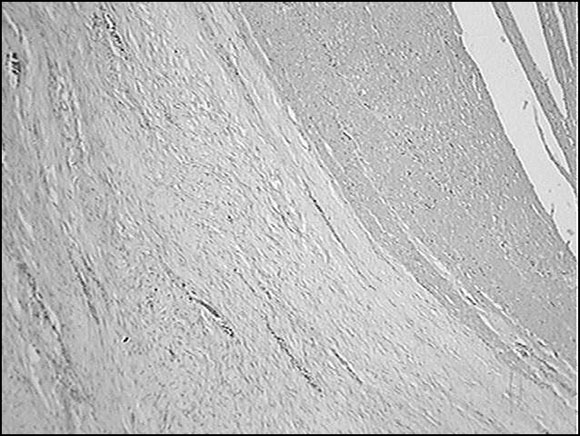

Figura 2: Esquema histológico del tumor donde se demuestra que es un tumor estromal y no muscular